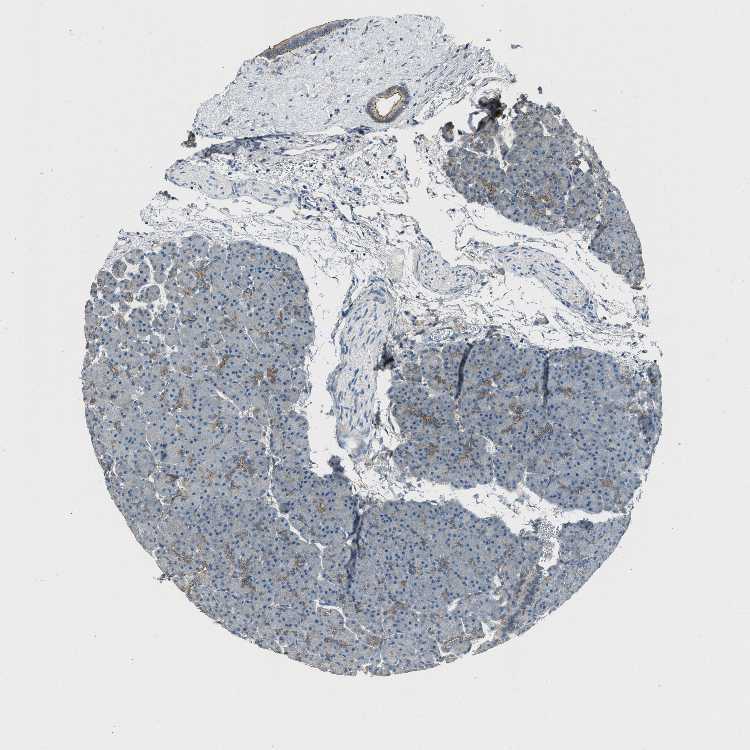

PANCREAS - Antibody stainingi

Antibody staining in the annotated cell types in the current human tissue is reported as not detected, low, medium, or high, based on conventional immunohistochemistry profiling in selected tissues. This score is based on the combination of the staining intensity and fraction of stained cells.

Each image is clickable and will lead to virtual microscopy that enables deeper exploration of all samples and also displays staining intensity scores, fraction scores and subcellular localization as well as patient and tissue information for each sample.

Antibody HPA020095Antibody HPA020138Antibody CAB010878Antibody CAB080402

Exocrine glandular cells MediumLowMediumHigh

Pancreatic endocrine cells LowNot detectedLowNot detected